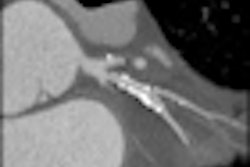

A growing body of evidence has demonstrated the value of coronary CT angiography (CTA) as an accurate, noninvasive modality to detect coronary artery stenoses and plaque, as well as predict future cardiac events. However, the small sample sizes used in many studies have limited their impact on public health policy, according to Dr. Hans-Christoph Becker and colleagues from Ludwig Maximilian University in Munich.

The results indicate CT-based findings of coronary plaque and stenosis are strong independent predictors of future cardiovascular events, Becker said at the ISCT conference.

The presence of significant coronary stenosis was associated with a tenfold higher risk for all cardiovascular events and a sixfold risk for death and unstable angina requiring hospitalization independent of coronary artery calcification, the researchers wrote in their study.

Becker pointed out during his presentation the results show there is a 4.5-fold risk associated with the presence of any coronary artery disease, and that each diseased coronary segment portends a 23% higher risk for adverse outcomes.